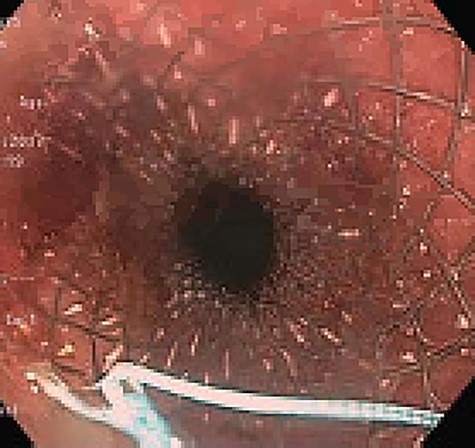

Approximately 2 months into his postoperative course, he returned with symptoms of dysphagia. esophagogastroduodenoscopy (EGD) revealed benign-appearing stenosis at the level of the esophagogastric anastomosis. This was initially dilated with a balloon. However, due to recurrent symptoms, a fully covered SEMS was placed to alleviate stricture (Figs 1, 2). The patient did well for nearly 2 months before returning with recurrent symptoms. A new web was visualized causing complete luminal obstruction (Fig. 3). This was unable to be traversed in antegrade fashion, requiring retrograde access via the jejunostomy utilizing guidewire. A pediatric colonoscope was able to be passed over the guidewire and dilate before subsequent SEMS deployment (Fig. 4). This stent was secured using 2-0 polypropylene suture via Overstitch device (Fig. 5). The initial SEMS was found to have migrated to the mid portion of the gastric conduit. However, due to the small caliber of the proximal stricture and to avoid disrupting newly deployed stent, the initial SEMS was left in place.

Retrograde guidewire, with subsequent pediatric colonoscope and SEMS placement.

SEMS placement across web, secured with 2-0 polypropylene suture via Overstitch device.